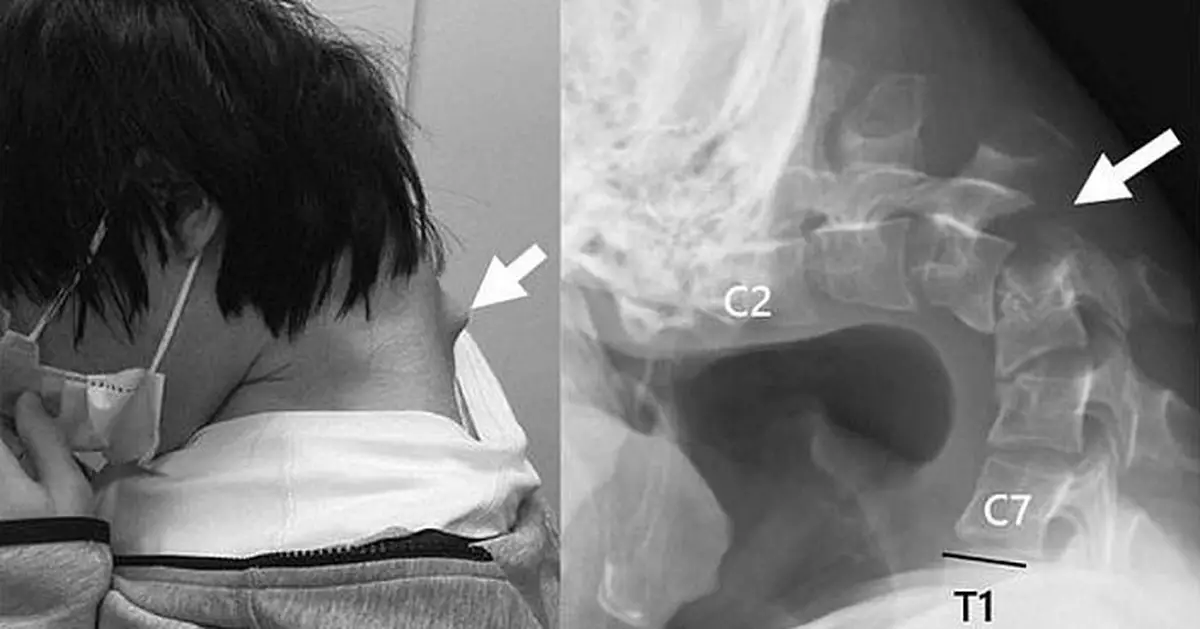

醫療團隊檢查發現,男子頸椎已變形移位且出現疤痕組織,如同長出一個角。團隊最初嘗試以護頸支撐矯正,但因患者感到麻木不適,遂改以手術治療。醫生於手術中切除部分變形頸椎骨與疤痕組織,再植入金屬螺絲及鋼釘固定骨架。

圖片來源:Science Direct